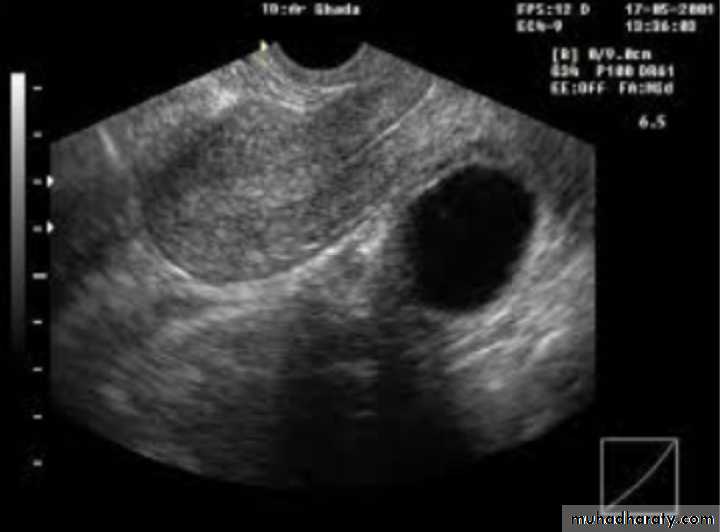

Dx: simple ovarian cyst

Description: round regular; smooth outline ;single echogenicity ;not contain blood ,contain only fluidTx:

-small and asymptomatic : conservative tx ;COCP

-large and symptomatic: surgical removal of cyst

Large simple ovarian cyst

Tx only surgical removal